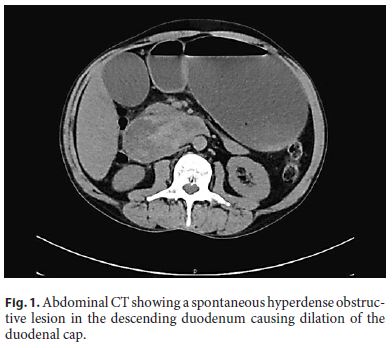

A 55-year-old alcohol-dependent man presented to the hospital for a 6-day history of epigastric pain radiating to the back, associated with nausea and uncontrollable vomiting. He denied any known coagulation disorder, recent abdominal trauma, or endoscopic/surgical intervention. Physical examination revealed scleral icterus, abdominal distention, and epigastric tenderness. Investigation identified hyperamylasemia (441 IU/L), high creatinine (6.02 mg/dL), and total serum bilirubin (2.89 mg/dL). Abdominal computed tomography (CT) performed without intravenous contrast enhancement showed duodenal distension with spontaneously hyperdense obstructive lesion in the descending duodenum and changes suggesting the presence of acute pancreatitis (Fig. 1). This was suggestive of an obstructive intramural duodenal hematoma (IDH) in the descending duodenum. A nasogastric decompression was performed, and the patient was kept on nil by mouth and treated with intravenous fluid hydration, parenteral nutrition, and proton pump inhibitor. The patient improved with remission of abdominal pain and vomiting as well as recovery of renal function. Three weeks later, abdominal magnetic resonance imaging demonstrated a marked reduction in the size of the IDH (Fig. 2).